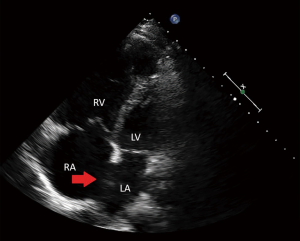

A 49-year-old female with a history of multiple strokes without evidence of atrial fibrillation or carotid disease presents for evaluation. 2D-TTE was suggestive of a patent foramen ovale (PFO), and she was referred for PFO closure with RT3D-TEE. Intra-procedure interrogation of the interatrial septum by 3D-TEE revealed a 9 mm secundum ASD with bidirectional shunting as opposed to a PFO (Figure 3). This information directly influenced device closure selection, and a 10 mm ASO device was selected. In a similar manner to patient #1, after correctly illustrating this patient’s atrial septal pathology, RT3D-TEE was used to ensure appropriateness of rim tissue to accommodate the ASO device. Post-deployment, 3D-TEE exhibited excellent device seal and purchase of all rim tissue without encroachment anteriorly in the aorta (Figure 4).